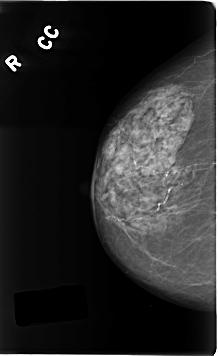

C_0196_1.RIGHT_CC

LEFT_CC LINES 4728 PIXELS_PER_LINE 2536 BITS_PER_PIXEL 12 RESOLUTION 50 OVERLAY

RIGHT_CC LINES 4616 PIXELS_PER_LINE 2824 BITS_PER_PIXEL 12 RESOLUTION 50 NON_OVERLAY